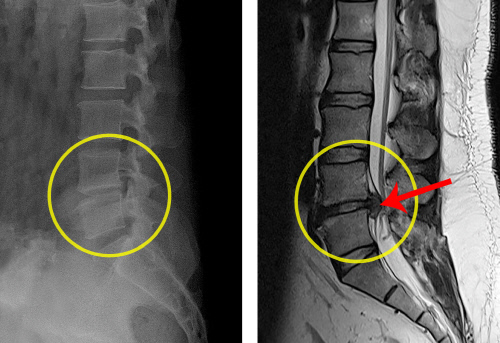

추운 겨울 스포츠를 즐기는 30대 K씨는 스노우보드를 타던 중 다리부위에 통증을 느껴 병원을 찾아 엑스레이 검사를 받았다. 검사 결과, 관절에는 아무 이상이 없다기에 주사치료와 약물치료, 물리치료를 받기로 했다. 얼마 후 더욱 통증이 심해져 다시 병원을 찾아 MRI 검사를 받았고, 허리디스크가 파열되었다는 진단을 받았다. K씨의 경우 엑스레이 검사로는 알 수 없었던 통증의 원인을 MRI 검사를 통해 분명하게 확인할 수 있었다.

또 최근 60대 L씨는 허리통증을 호소하며 가까운 의원에서 엑스레이 검사를 받았다. 큰 이상이 없다는 소견을 들었고 의사의 처방에 따라 물리치료를 받았다. 그러나 꾸준히 물리치료와 약물치료를 했음에도 불구하고 통증은 더욱 심해졌다. 결국 MRI 검사를 받고서야 통증의 정확한 원인을 밝혀낼 수 있었다. B씨는 허리디스크 파열이라는 진단을 받았고, 수술 후 회복됐다.

의료진이 허리 통증으로 병원에 온 환자에게 가장 기본적으로 하는 것은 엑스레이 검사다. 뼈의 이상 여부를 빠르게 확인할 수 있고 비용도 저렴하다. 하지만 허리는 뼈만 있는 것이 아니다. 척추뼈 외에도 추간판, 주변 인대, 근육, 신경, 혈관 등 다양한 구조물들로 구성돼 있다. 뼈의 이상으로 병이 생기는 경우는 20%도 되지 않는다. 엑스레이로는 보이지 않는 추간판, 신경의 이상으로 인한 질환인 경우가 80% 이상이다. 따라서 엑스레이 검사만으로는 명확한 원인을 찾지 못하고 치료시기를 놓쳐 증상이 악화되는 경우가 다반사다.

골절과 같이 명확한 질환 판명이 가능한 경우 엑스레이 검사만으로도 진단이 가능하다. 하지만 디스크질환이나 협착증과 같은 질환은 정확한 진단을 위해서 MRI 검사 등의 추가적인 검사가 필요하다. 위의 사례처럼 엑스레이 검사 결과 이상이 없고, 비수술적 치료에도 불구하고 감각이상, 근력저하 증상, 치료에 반응 없는 지속적인 통증, 극심한 통증이 지속된다면 MRI 검사가 시행돼야 한다. 수술 후 결과를 정확하게 확인하기 위해 MRI 검사가 필요할 때도 있다.

![[힘찬병원] 허리디스크 환자의 엑스레이와 MRI(오른쪽)검사결과](https://file.sportsseoul.com/news/legacy/2020/11/16/news/2020111601000926800065921.jpg)